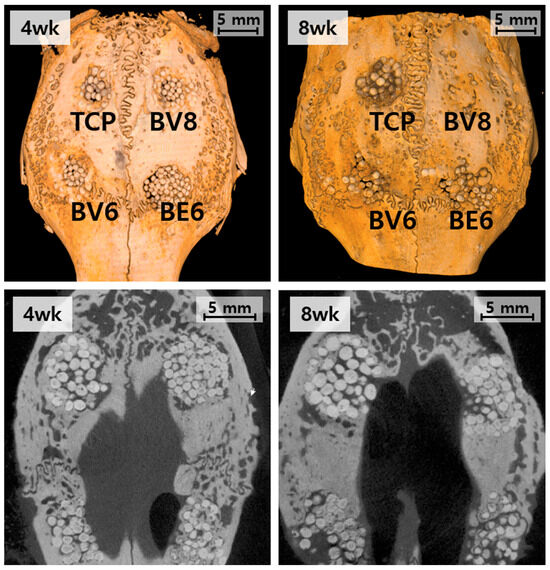

Bone graft substitutes are extensively investigated for addressing critical-size bone defects; however, their efficacy is limited by inadequate bone regeneration and subpar handling properties. Herein, we compared the bone regenerative capacity of CaO–SiO2–P2O5–B2O3-based [...] Read more.

Bone graft substitutes are extensively investigated for addressing critical-size bone defects; however, their efficacy is limited by inadequate bone regeneration and subpar handling properties. Herein, we compared the bone regenerative capacity of CaO–SiO2–P2O5–B2O3-based bioactive glass (BGS-7) macrobeads with that of β-tricalcium phosphate (β-TCP) beads and evaluated their performance when incorporated into hydrogels to improve their handling properties. BGS-7 macrobeads were fabricated via alginate crosslinking and heat treatment, and their physicochemical properties and microstructures were characterized. In a rabbit calvarial defect model, BGS-7 macrobeads, heat-treated at 600 and 800 °C, exhibited superior bone bridging and degradation than size-matched β-TCP macrobeads. To further evaluate their regenerative potential, critical-size defects (6 mm diameter × 10 mm depth) were created in the rabbit femoral condyle. To enhance clinical applicability, BGS-7 beads were incorporated into cellulose-based hydrogels and implanted into the defects. Radiographic and histomorphometric analyses demonstrated that bone formation and stable fixation achieved with hydrogel formulations containing BGS-7 microbeads and Laponite were more pronounced than those with BGS-7 beads alone. The findings suggest that BGS-7 macrobeads, particularly when combined with microbead- and Laponite-containing hydrogels, represent a promising bone graft substitute with improved regenerative and handling properties compared with using BGS-7 beads alone. Full article